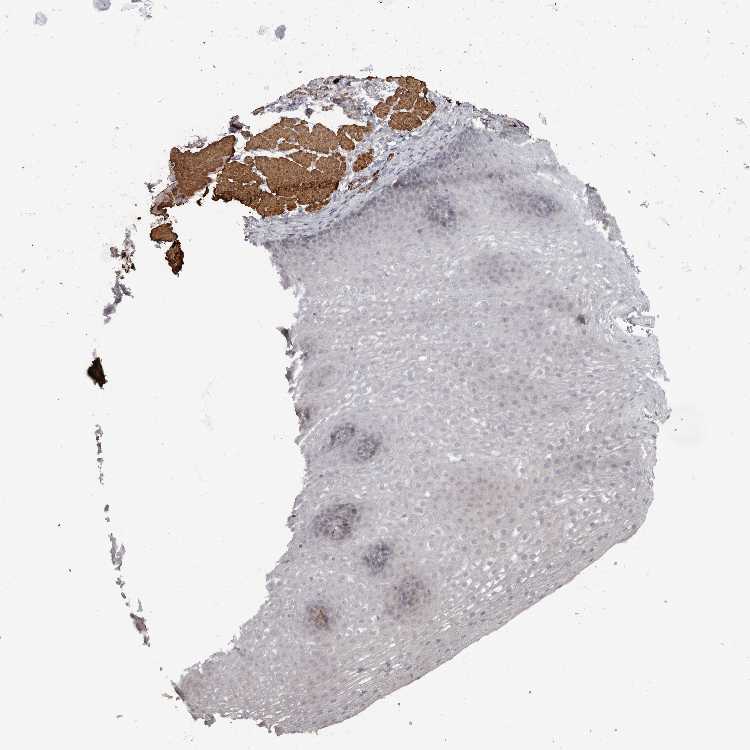

ESOPHAGUS - Antibody stainingi

Antibody staining in the annotated cell types in the current human tissue is reported as not detected, low, medium, or high, based on conventional immunohistochemistry profiling in selected tissues. This score is based on the combination of the staining intensity and fraction of stained cells.

Each image is clickable and will lead to virtual microscopy that enables deeper exploration of all samples and also displays staining intensity scores, fraction scores and subcellular localization as well as patient and tissue information for each sample.

Antibody HPA027175

Squamous epithelial cells Not detected